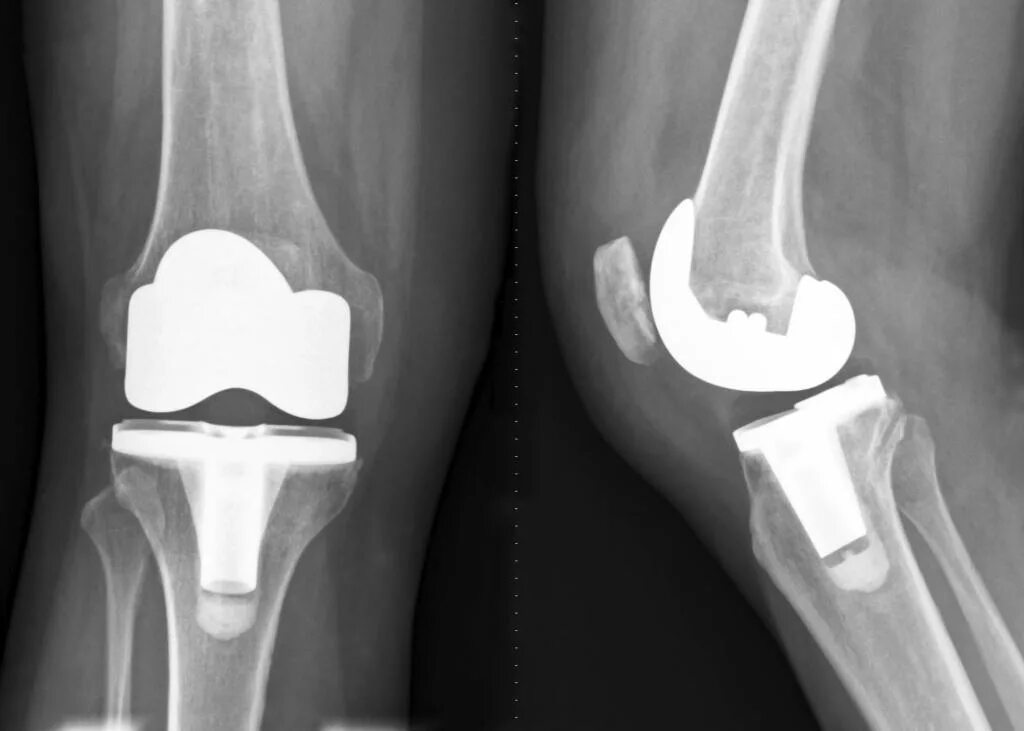

Операция протезирование сустава